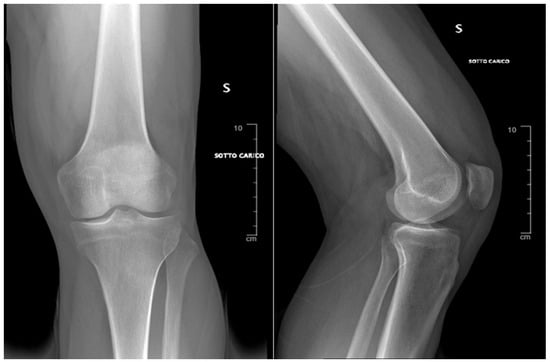

3. Results